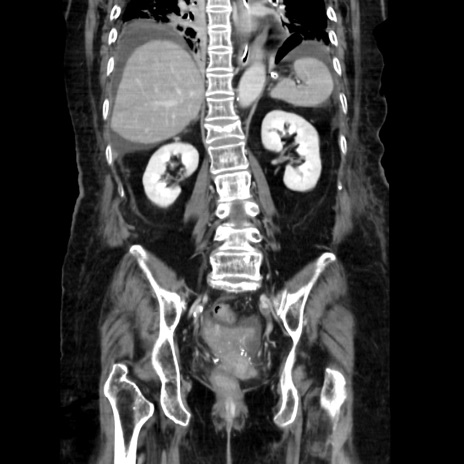

症例40(冠状断像)

【症例】90歳代女性

【主訴】腹痛・嘔吐

【現病歴】 食欲低下、嘔吐があり昨日他院受診。肺炎と診断され入院となる。入院後より腹部全体に圧痛あり。胃管留置され経過みていたが、症状持続するため、

当院転院となる。

【既往歴】胸椎圧迫骨折、胆石症

【身体所見】腹部:中央に激痛あり、圧痛あり、反跳痛不明

【データ】WBC 17100、CRP 18.82

冠状断像